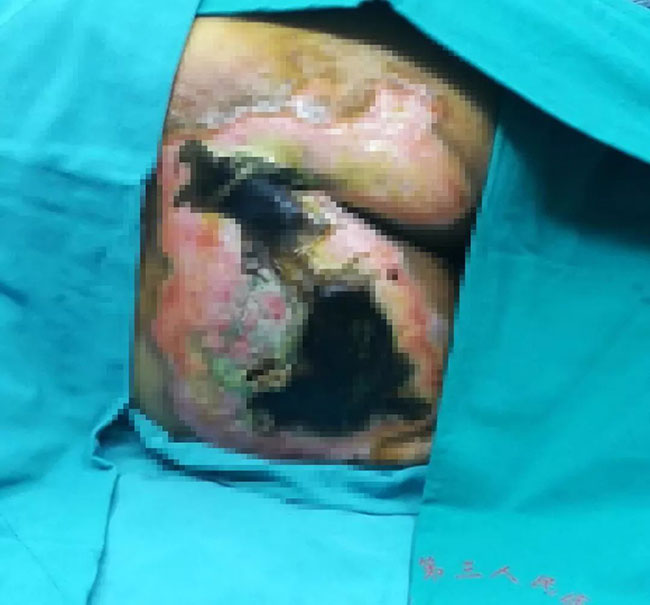

患者胡XX,,,,,,今年81岁,,,,,,中风后导致左侧肢体瘫痪。。。2017年11月份,,,,,,用中药熏蒸臀部,,,,,,不小心烫伤皮肤,,,,,,导致他双侧臀部起了水泡。。。自行买药外敷后情形没有好转,,,,,,并逐渐泛起皮肤脱落、红肿加重的状态,,,,,,臀部受压几天后,,,,,,情形越发严重,,,,,,局部皮肤坏死变黑了。。。

2017年12月1日,,,,,,患者被送到广西江滨医院通俗外科,,,,,,经诊治,,,,,,为烫伤后导致的压疮,,,,,,创面淤黑、坏死,,,,,,面积为17cm×17cm。。。

在对创面举行消炎处置惩罚后,,,,,,2017年12月5日,,,,,,广西江滨医院通俗外科李碧锦主任接纳皮肤原位再生医疗手艺为患者举行了清创手术,,,,,,剔除坏死组织,,,,,,敷上烧伤膏,,,,,,加上全心照顾护士,,,,,,患者的创面逐渐生长出了新的肉芽组织,,,,,,皮肤最先原位再生。。。